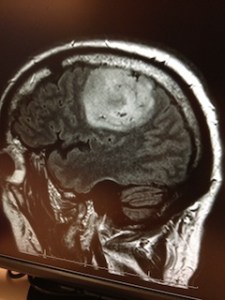

I got the diagnosis a couple weeks ago and have since been living the life of someone who has just found out they have brain cancer. My rockin’ neurosurgeon, Dr. Frank Coufal at Scripps Memorial in La Jolla, removed the large mass of it two weeks ago. I hung around ICU for about a week after that before I was released home. Since then, I have been meeting with the people who will make me all better. If you’re into the specifics of these types of things— it’s a grade 3, primary brain tumor called Anaplastic Astrocytoma, an aggressive type of brain cancer in my left frontal lobe. As a side note: that’s the area that controls speech, not optimum when you make your living as a San Diego Anchorman. Thankfully, I only lost my speech for a short while. The doctors tell me I have between 1 and 3 years to live.

P.S. Here are photos of my brain before and after the surgery. Pretty cool, huh?

[Above: Before Surgery/Below: After Surgery]